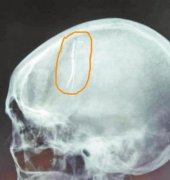

女子大脑藏七厘米长针几十年取出已完全生锈(图)

核心提示| 脑子里藏着一根六七厘米长的钢针,且已经完全生锈,估计已有几十年的时间。这种怪事你相信吗?不久前,在洛阳一医院就出现了这样一起病例。 经常头疼原因在于脑中藏针 今年58岁的王晓红(化名),家庭和睦,日子过得顺风顺水。不过在美满生活之外,